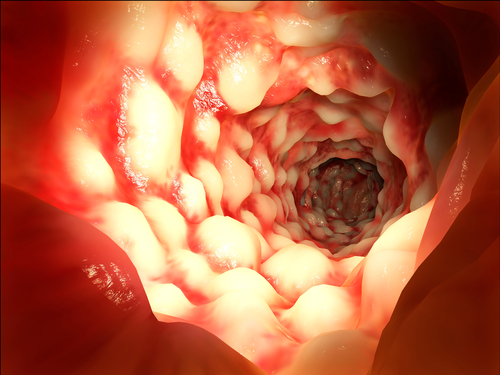

אינטראקציות משתנות בין מערכת החיסון הרירית למיקרוביום במעי תורמות לפתוגנזה של מחלות מעי דלקתיות (inflammatory bowel diseases –יIBD). לא ברור כיצד משפיעים מעכבי ציטוקינים, כמו אנטגוניסטים של tumor necrosis factorי(anti-TNF), על המיקרוביום במעי.

במחקר זה, נבדקו ההשפעות של anti-TNF על מבנה ותפקוד "קהילת" חיידקי המעי, במחקר אורכי דו-שלבי שכלל מטופלים עם IBD. החוקרים בדקו את הקשר בין ממצאי הבדיקה לבין תוצאות הטיפול וחקרו את דפוסי המטבוליטים בדגימות צואה לפני ואחרי הטיפול ב-anti-TNF.